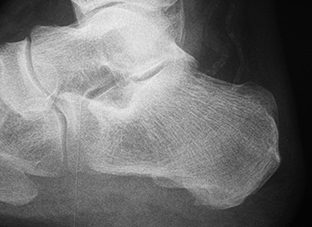

La aponeurosis plantar es más gruesa en pacientes con fascitis, grosores de 4,95 a 6,1 mm frente a 3,22 a 4,0 mm en sujetos sin patología [41][42]. El engrosamiento de la fascia ≥4 mm se asocia con la fascitis plantar, aunque también se ha encontrado en el 21% de los casos asintomáticos [43].

El grosor de la fascia es fundamental para indicar la cirugía en la fascitis [44]. Una fascitis plantar con un grosor ecográfico superior a 4 mm no mejorará con ningún tratamiento conservador y ningún paciente debería ser intervenido con un grosor de la aponeurosis plantar inferior a 5 mm [45].

La fascitis plantar es una patología de las partes blandas y su diagnóstico no se puede basar únicamente en la imagen radiográfica de un espolón del calcáneo o calcificaciones bien estén en la inserción del tendón de Aquiles o en el origen de la fascia plantar [46]. Por eso, la ecografía es el método de diagnóstico de referencia para la evaluación de los trastornos de la fascia plantar [47], pues su precisión y fiabilidad son comparables a la RM y es más rápida, económica y accesible [30][44-49] (Figura 2)

Figura 2A

Figura 2B

Figura 2C

Figura 2. A) Imagen ecográfica de la aponeurosis plantar. B) medición del grosor de la aponeurosis plantar. C) RM sagital del pie